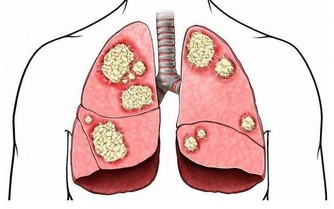

丙肝也是一種常見的病毒性肝炎,是導致肝硬化、肝癌的主要原因之一,但是它的篩查率和治療率遠低於乙肝。

丙肝和其他病毒性肝炎不同,它不容易被人體的免疫系統識別,這樣就很容易潛伏在人體內,病毒就會慢慢地損害肝細胞,從而危害人體。沒有得到及時治療的丙肝患者,就會逐漸發展成肝硬化,甚至是肝癌。

還有一點,丙肝和乙肝有著不同,那就是乙肝病毒攜帶者如果僅乙肝表面抗原呈陽性,但是轉氨酶正常,也就是說肝功能正常,可以不做治療,定期檢查即可。但是,丙肝患者則不行,只要發現感染了丙肝病毒,就需要及時治療,不然病情會越來越嚴重。